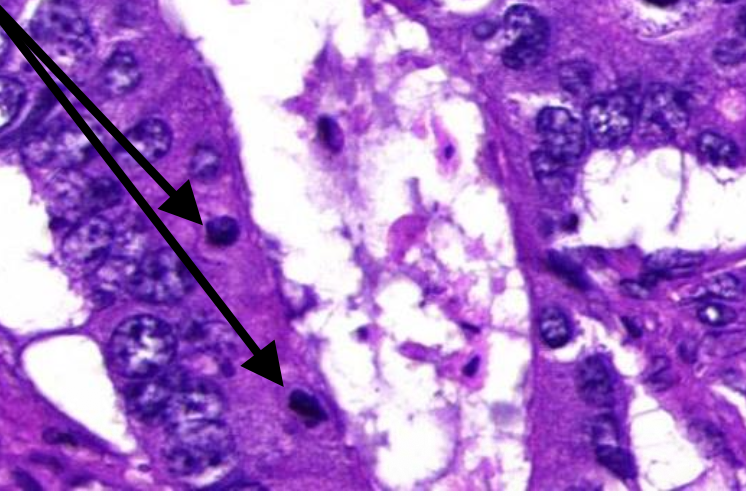

Jichtophus: pathologische veranderingen

onder dermis:opstapeling van uraat kristallen (=fijne witte naalden en amorfe hematoxifiele structuren )

inflammatoire reactie: lymfocyten, macrofagen & reuscellen

welk preparaat

jichtophus

jichtophus: wat zie je op deze uitvergroting

stapeling van uraatkristallen onder de dermis